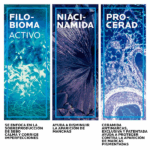

PHYLOBIOMA

Se focaliza en la sobreproducción de sebo y reduce el crecimiento de la bacteria C.Acnes IA1, calmando y corrigiendo las imperfecciones. Gracias a la ciencia del microbioma se ha demostrado clínicamente que reduce el biofilm, la inflamación y la hiperqueratinización.

PROCERAD TM

La ceramida antimanchas, exclusiva y patentada, que ayuda a proteger contra la aparición de marcas rosas/marrones.

10% NIACINAMIDA

Ayuda a difuminar la apariencia de las manchas oscuras y la pigmentación.